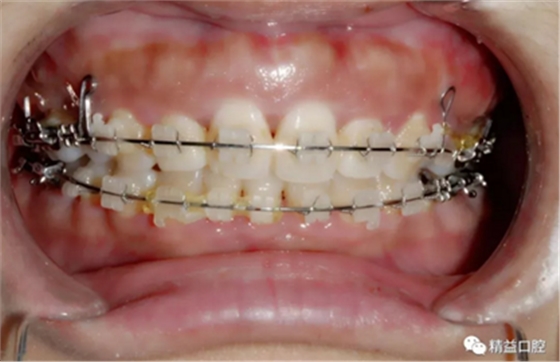

內(nèi)收過程中,李醫(yī)生在上頜左右各植入一顆支抗釘,以達到更好的內(nèi)收效果。

因下頜唇傾比較嚴重,加上門牙牙根在矯正前已經(jīng)有大量吸收前提下,為了實現(xiàn)更好的矯正效果,李醫(yī)生選擇了拔除下頜左一,內(nèi)收下牙,給上牙內(nèi)收提供更多的空間。

短短兩年時間,俊嚴重前突的牙齒在經(jīng)過拔牙,打支抗釘,打各種曲,戴各種皮筋的“不斷折騰”下,完美蛻變。